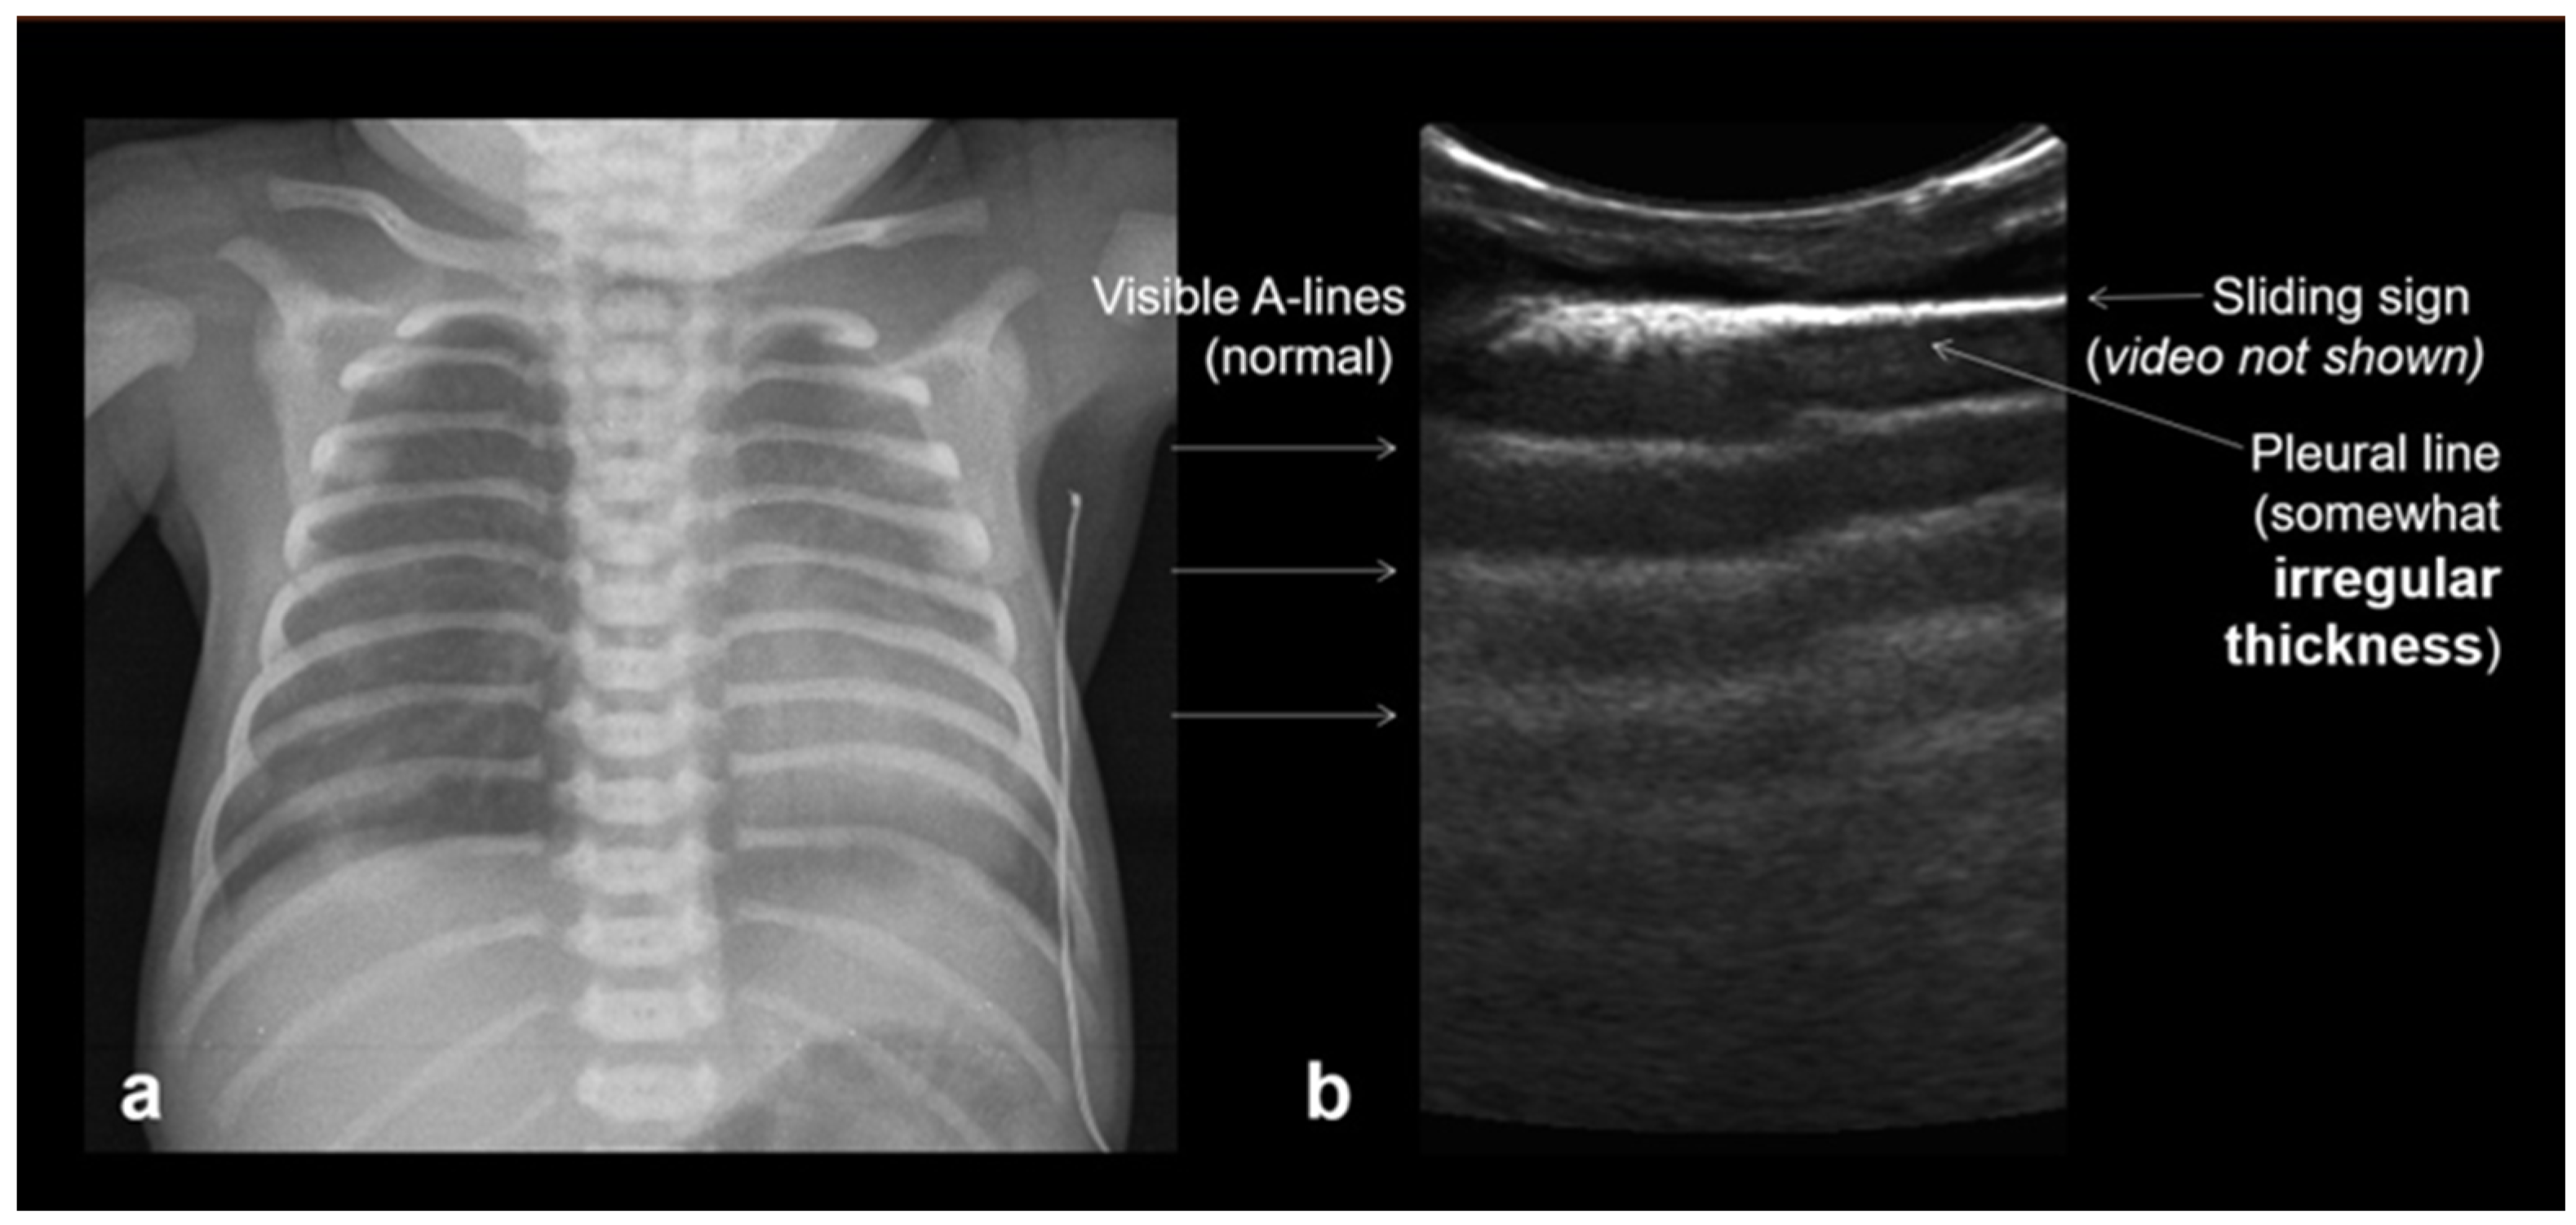

3.1.3. Pleural Line

3.1.4. Sliding Lung Sign

3.1.5. Sea-Shore Sign